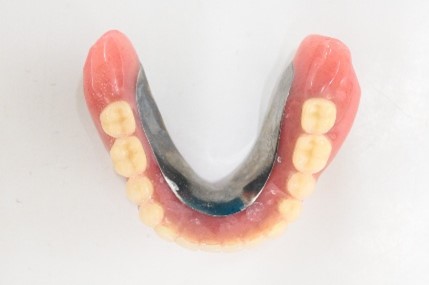

【マグネット式総入れ歯】

上顎

下顎